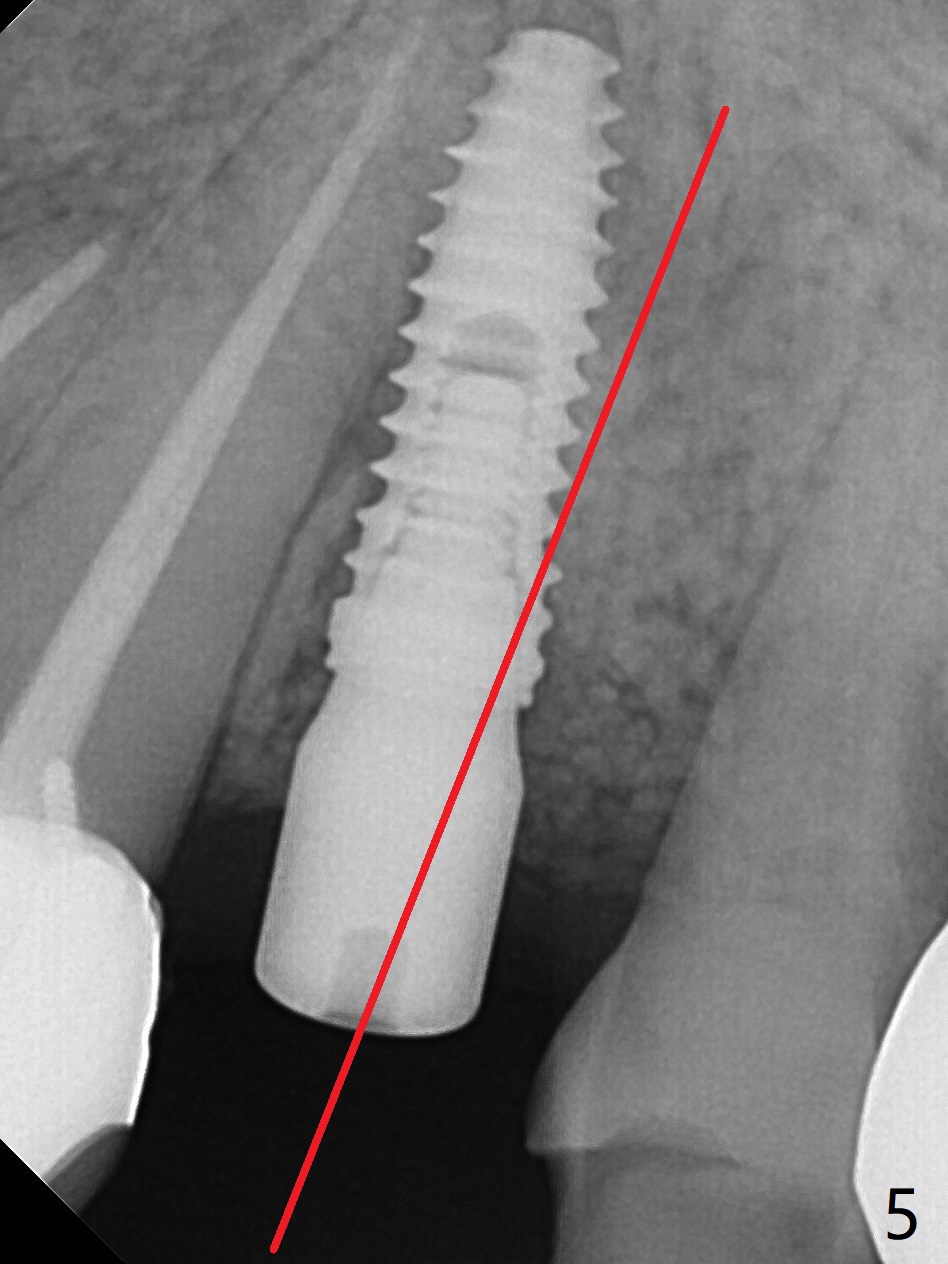

植骨后6个月牙槽窝愈合正常,角化龈和牙槽嵴都宽(图一),导板种植好像不需要切口。利用导板植入,但是离尖牙牙根很近(图二,三)。取出植体后,准备切开改变钻洞方向(图四,五),结果效果不错(图六,七),腭侧骨壁低,安置愈合基台,植骨(图八:*),覆盖胎盘膜,缝合。